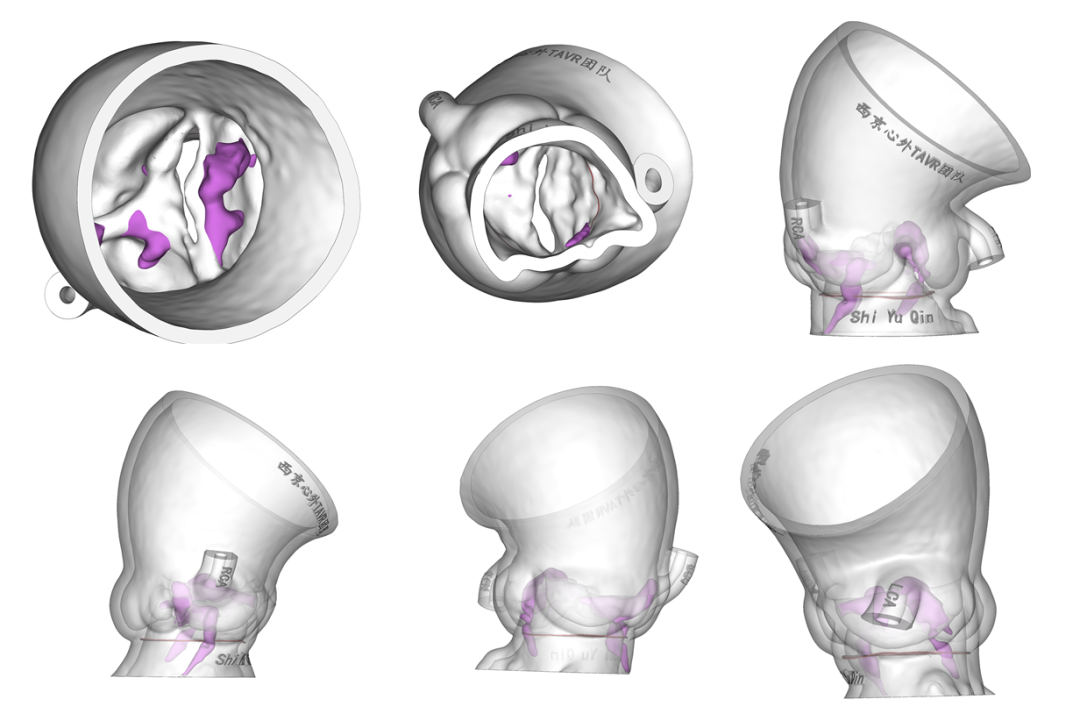

术前3D模型评估:

术前讨论:

基于术前超声、CT及3D模型多模态影像分析,患者合并冠脉病变,未来需处理冠脉的可能性较大,采用长支架自膨瓣膜后期冠脉干预难度较大。同时,Type1型二叶瓣,且瓣环的两处明显团块钙化延伸至LVOT深度>5mm(12.3mm),长支架自膨瓣术后瓣周漏风险较高。综合考虑后拟选用Prizvalve球扩TAVR瓣膜,便于未来冠脉干预。此外,患者左冠开口平面可见瓣叶,瓣尖有较大团块钙化,左冠开口阻塞风险较大,拟行术中左冠保护。

针对瓣膜型号选择,根据主动脉瓣环面积631.1mm2折算直径28.3mm,LVOT29.0mm,按照常规标准需选择29mm PrizValve。因患者瓣叶为极重度钙化(Hu850钙化积分2322),瓣膜型号可适当downsize,应能较好在瓣膜位置锚定,也有利于减少冠脉开口阻塞风险。

综合评估后,拟采用右侧股动脉入路,25mm球囊预扩张、Balloon sizing并观察冠脉阻塞风险,左冠支架保护,26mmPrizvalve标准容量球囊扩张TAVR手术。